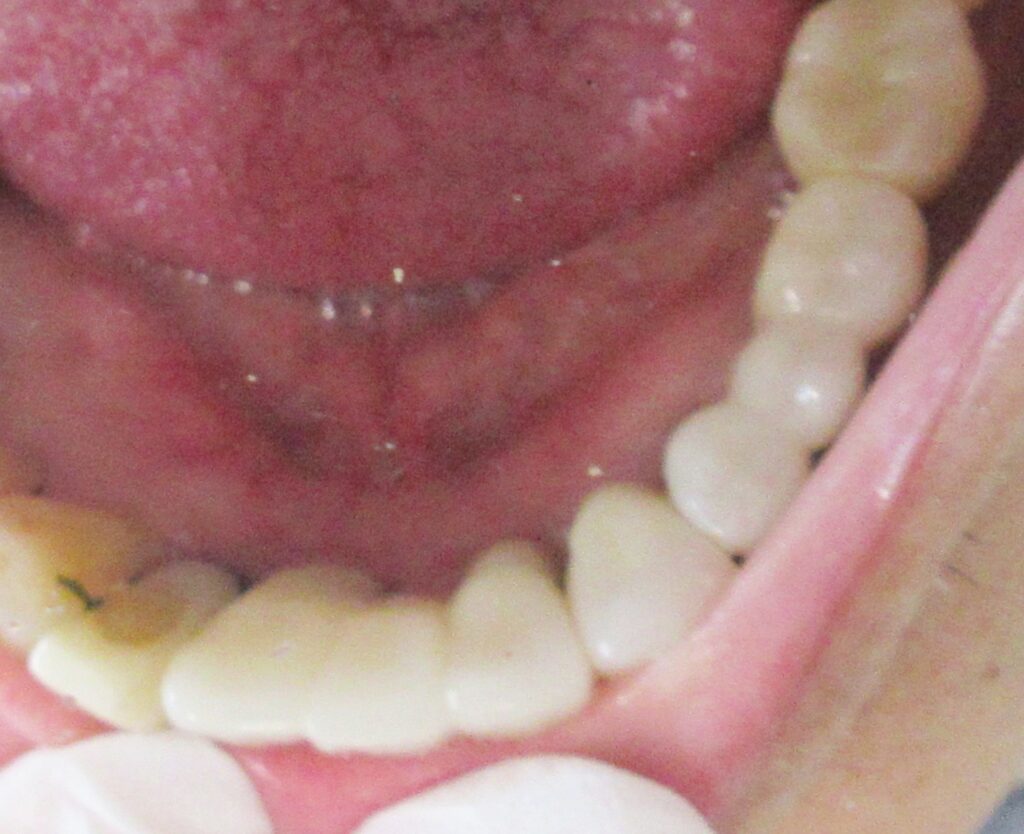

その後は定期的にお掃除や検診に通院していただき、約3か月経過した後に、きれいな差し歯が入りました。